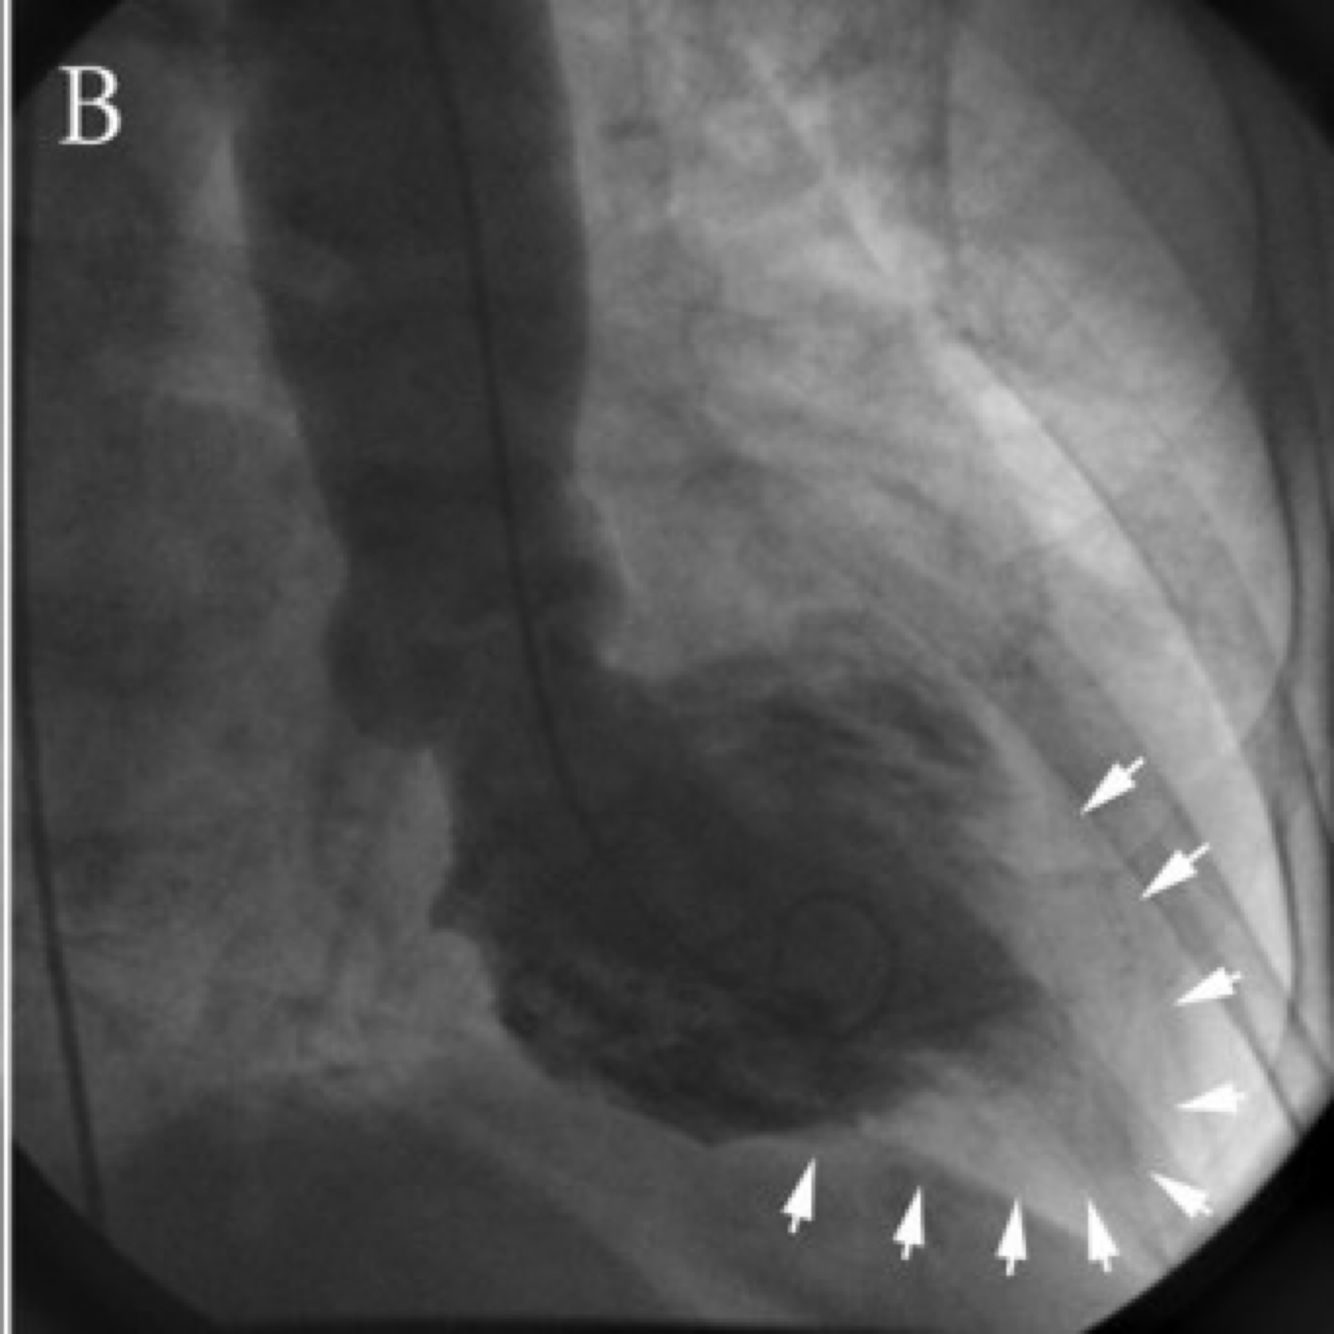

A

How well did you know this?